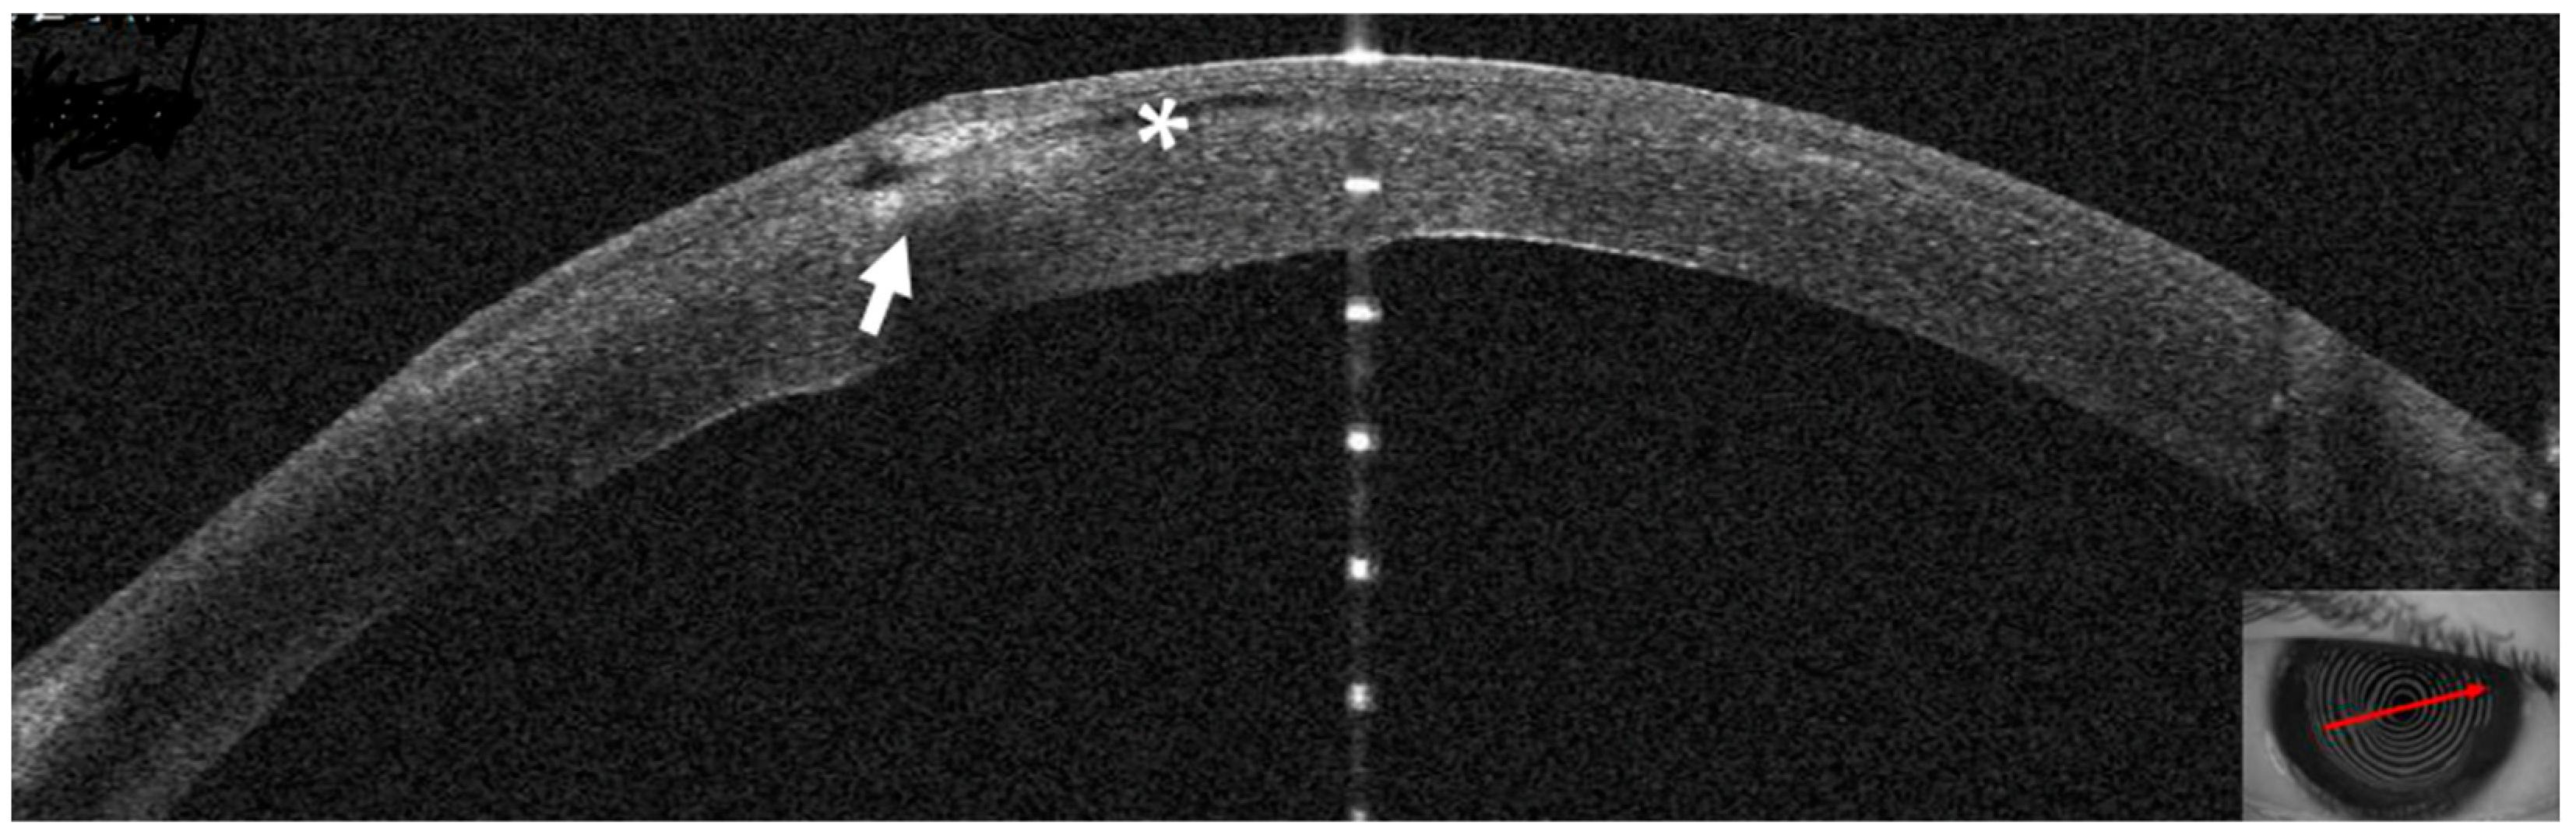

3.2. Patient #2